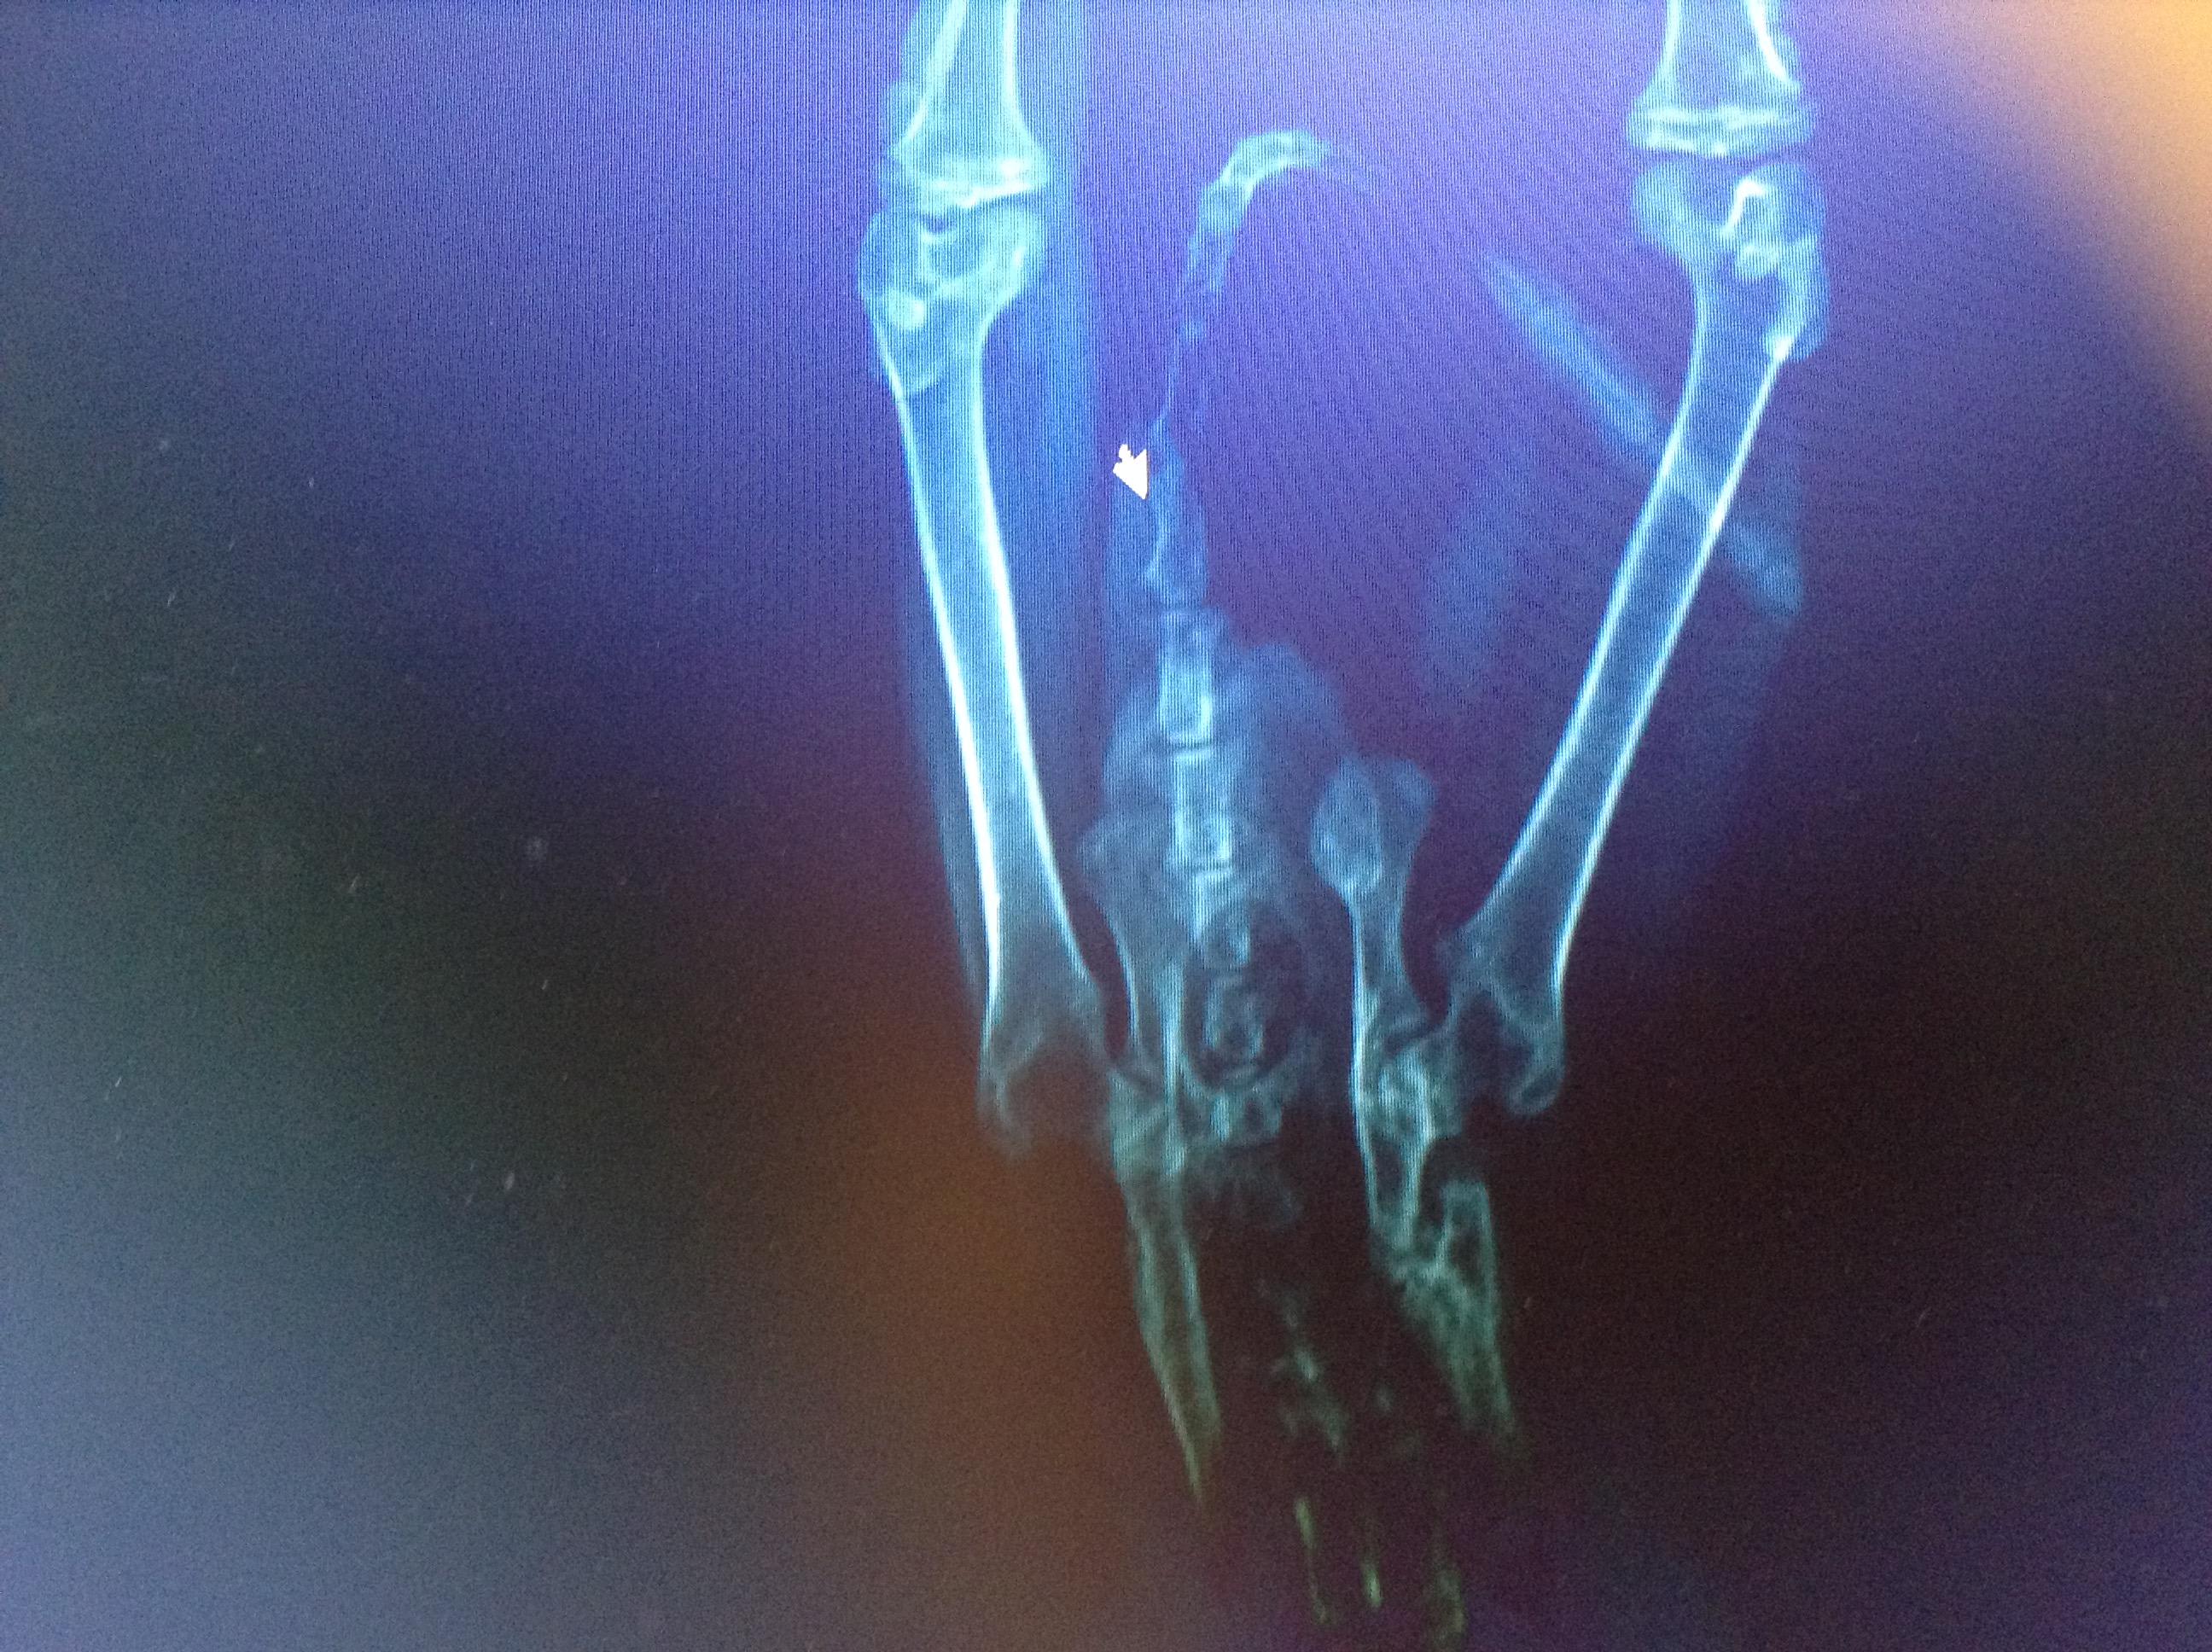

Loss of Bowel Control - cat. Broken pelvis from RTA. Goes in litter tray but faeces drops out throughout the day & when sleeping. Stopped around the time she went into season & for approx 4 weeks after she was neutered but has just started again in past couple of days. Any ideas on how to help her? She is a feral cat, approx 6 months old that we rescued & were hoping to rehome (animal rescue group) as extremely friendly. We have tried intestinal food as drops aren't fully formed.

This question includes photos that may contain sensitive content. Click to view.

That is unfortunately a very bad sign, if she is suffering from neurological damage that is affecting the ability to pass stools then her prognosis will be very bad. you need to ask your vet regarding her pelvic, if it is fractured then this could be the cause of her not being able to pass stools and this will need to be repaired surgically ASAP.